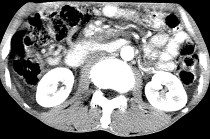

- 单项选择题女,50岁, 中上腹疼痛,消瘦乏力, 影像检查如下图,最佳的诊断是  (    )

- A、慢性胰腺炎

- B、急性胰腺炎

- C、胰腺癌并腹膜后淋巴结转移

- D、胰岛素瘤

- E、腹膜后淋巴瘤